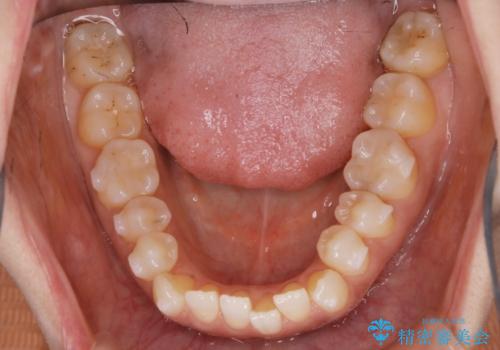

【非抜歯】短期間で実現する前歯の反対咬合治療

- 前歯のガタつきを主訴に来院されました。

奥歯の噛み合わせにはほとんど問題が見られず、歯列拡大とIPRのみの必要最低限の移動で歯並びの治療を計画することとなりました。

拡大とIPR

歯列の幅を拡大することにより作れるスペースは想像より大きく、実際に拡大だけでガタつきが治せるというケースもあります。

その他の歯のガタつきをとるためのスペース作りの方法の一つにディスキング(IPR)という方法があります。

歯と歯の間を一ケ所あたり最大0.5mmまでの範囲内で削ることで歯自体が少し小さくなり、それにより作られるスペースを数ヶ所分合わせることで合計で数mmの大きなスペースが作れるという方法です。